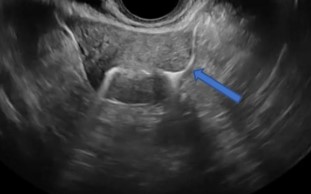

Παράδειγμα Υπερηχογραφικής σαλπιγγογραφίας HYFOSY βέλος : όπου φαίνεται διαπερατότητα, υπερηχογενές σκιαγραφικό στην αριστερή σάλπιγγα με ροή

HYFOSY 3D

Παράδειγμα Υπερηχογραφικής σαλπιγγογραφίας HYFOSY με τρισδιάστατη απεικόνιση ενδομητρικής κοιλότητας και σαλπιγγικής διαπερατότητας